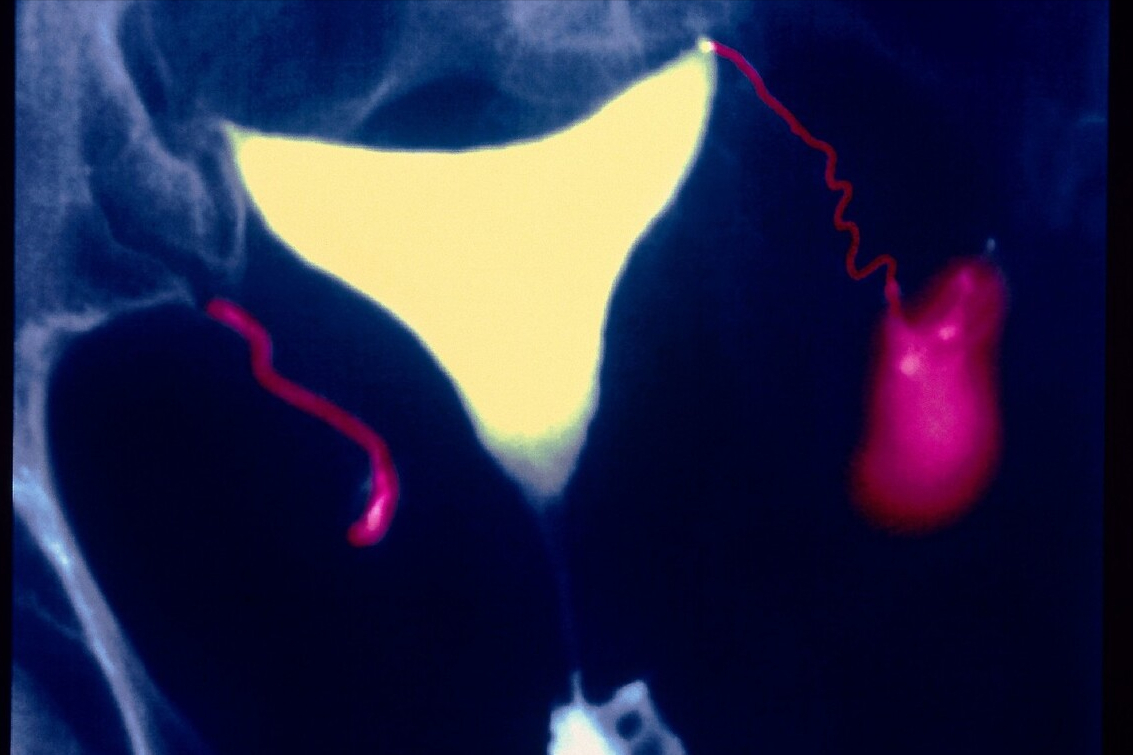

输卵管积水确实是困扰临床医生的令人头疼的问题。输卵管积水是引起不孕的主要原因之一,临床上非常常见,多见于反复人工流产、宫外孕、剖宫产术后,而积水的存在又降低试管婴儿的成功率,临床上处理非常棘手。

对于这类病人,治疗原则就是果断进行腹腔镜下积水侧输卵管近端结扎+远端积水引流及伞端成型术。术后再进行胚胎移植,临床妊娠率大大提高。

当然,要警惕,有很多输卵管积水的患者,新鲜胚胎移植会发生宫外孕,原因不明。因此,对于输卵管积水不是很严重的患者,假如这个患者又不想做腹腔镜手术,可以采用全胚冷冻,进行冻胚周期移植,在移植前1-2天抽吸输卵管积水,还是有较高的临床妊娠率!当然,也要做好失败的心理准备,如果反复失败,还是建议做腹腔镜下输卵管结扎+积水伞端造口+积水引流术。